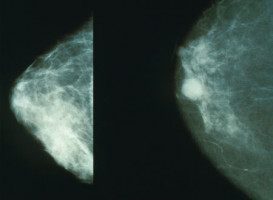

According to McCarthy, breast density refers to the amount of fibroglandular tissue in the breast when observed on a mammogram.

Fibroglandular tissue appears as white on the mammogram, making it difficult to visually detect breast cancers.

Traditionally, radiologists examine mammograms and assign patients a breast density level; however, this assignment can be subjective, McCarthy said.

Instead, in this study, McCarthy and colleagues used fully automated computer algorithms to produce both the conventional two dimensional breast density measurement and a three-dimensional volumetric estimate of breast density.